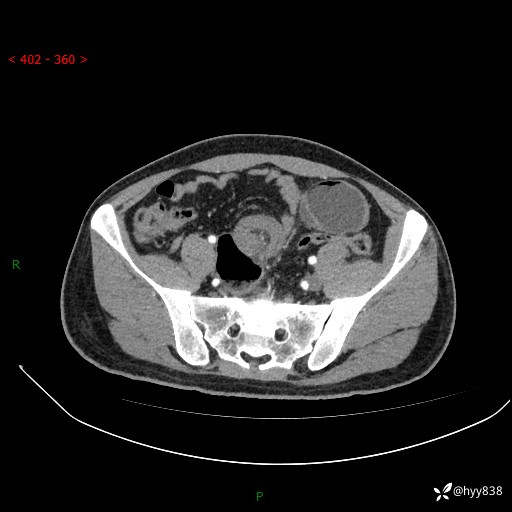

年轻男性,腹痛5月余。除了肠梗阻,你还能看到什么---结果公布~

主诉:腹痛5月余。

现病史:患者于5月前无明显诱因开始出现腹痛,上明显,为间断性胀痛不适,无畏寒发热,无心慌气促等特殊不适,遂来我院。我院门诊遂以“腹痛原因待查”收入我科。 起病以来,患者精神、饮食、睡眠欠佳,大小便正常。体力体重无明显变化。

腹部CT增强扫描(动脉期+静脉期)